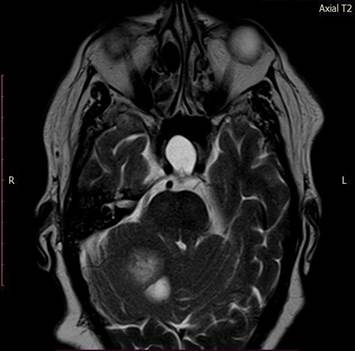

A ressonância magnética de crânio evidenciou grande lesão sólido-cística no corpo medular do cerebelo à direita, com efeito expansivo significativo (Figura 1).

A lesão, com dimensões 30,9x32,0x36,4, apresentou hipersinal em T2 (Figura 2) e FLAIR (Figura 3), hipossinal em T2, depósitos de hemossiderina nas bordas, área de restrição à difusão e intenso realce pós-contraste na porção sólida. As áreas císticas sugerem alto grau de necrose.

Figura 2. Ressonância magnética de crânio axial T2